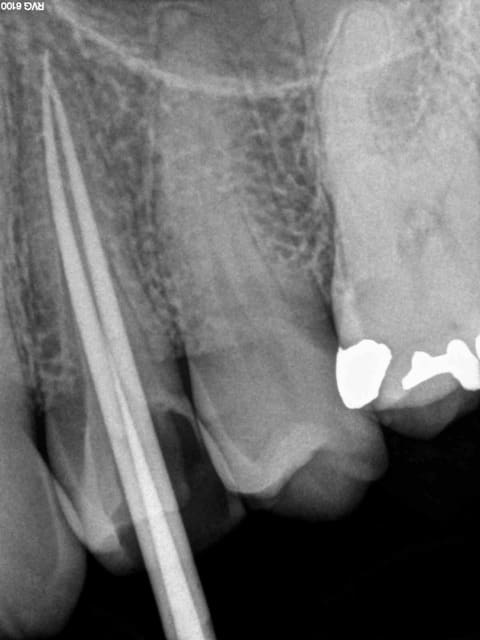

signes radios:espace desmodontal inf à 1mm

pas d'image apicale

lamina dura normal

pas de résorption apparente

obturation dense confinée à l'espace endo et

semblant atteindre la jonction cémento dentinaire(à un mm

de l'apex anatomique environ)

autrement quand je fais un RTE avec lésion apicale visible à la radio je me laisse environ 6 mois pour le contrôle de guérison